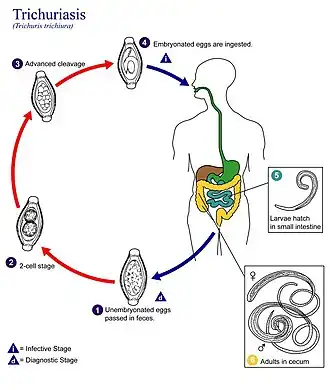

| Ciclo de vida do Trichuris trichiura | |

Ciclo de vida

Os ovos são expelidos com as fezes e permanecem viáveis durante vários meses ou anos em solo úmido e quente, e são infecciosos assim que se desenvolve a larva no seu interior, o que demora algumas semanas. Se ingeridas, as larvas saem dos ovos no lúmen do intestino, migram para o ceco e penetram na mucosa intestinal. Aí se desenvolvem, maturando em formas adultas depois de alguns meses, que permanecem com a cauda no lúmen do intestino e a cabeça penetrando a mucosa. Se houver um macho e uma fêmea, pelo menos, no mesmo indivíduo, acasalam e a fêmea põe mais de 2000 ovos por dia, excretados nas fezes. As formas adultas podem sobreviver durante vários anos. Alimentam-se do bolo intestinal mas também de sangue. São semelhante ao Ascaris lumbricoides. Os vermes podem viver de um a cinco anos dentro do intestino humano sem nunca causar sintomas.[12]